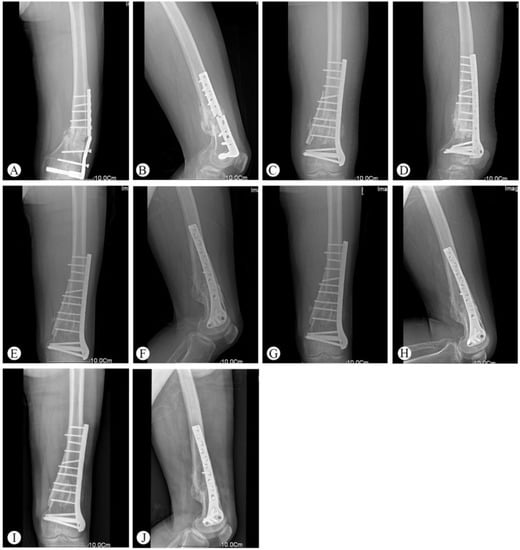

One patient had a deep infection five days after the operation and underwent a secondary surgery (implant removal and external fixation). There were two patients who had minor surgical complications, including one superficial wound infection and one partial wound dehiscence. After debridement and suturing, both patients’ complications were resolved. One patient with nonunion required bone grafting without hardware exchange. Post-traumatic arthritis was seen in one patient at the final follow-up, which was based on the radiologic assessment (Table 2). Typical cases are shown in Figure 1 (Patient 2), Figure 2 (Patient 5), and Figure 3 (Patient 10).

Figure 2. Representative images of Patient 5 (29-year-old male who suffered a heavy object crush to his left thigh). (A,B) X-ray at admission. (C,D) X-ray 5 days after the operation. (E,F) Follow-up X-ray at 3 months. (G,H) Follow-up X-ray at 30 months. (I) Full-length radiography showing the lower limb at a 33-month follow-up visit. Limb alignment and length was good. (J,K) Range of knee joint motion at a 33-month follow-up visit. The patient achieved full knee extension. However, the range of knee flexion was only 90°.